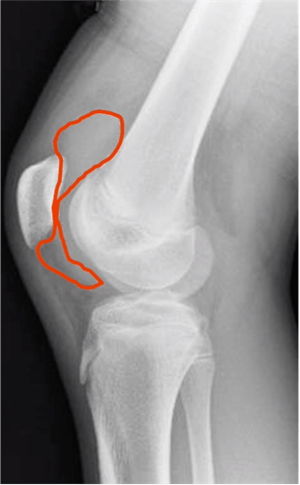

- X-ray – side view image of the knee

- Look at the kneecap as it is related to the thigh bone.

- Look at the muscle coming off the kneecap

- Look at the space between the kneecap and the femur

- If there is a curvilinear density that is not the linear muscle, not the deep muscle or the fat pad, it is most likely an effusion.